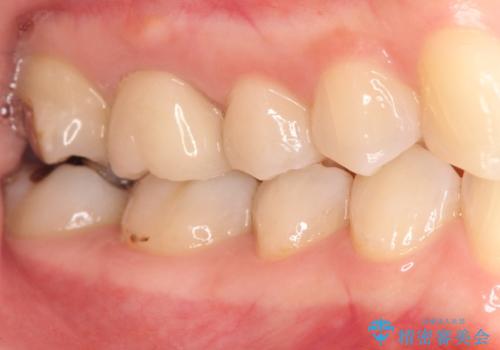

[フルジルコニアクラウン] 老朽化した銀歯を白く